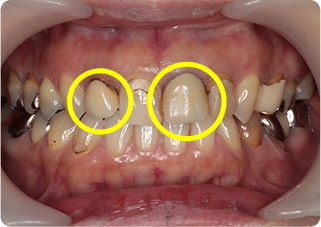

セラミッククラウン症例②

術前

仮歯

術後

| 主訴 | 前歯を綺麗にしたい、隙間が気になる |

| 治療期間/回数 | 4ヵ月、6回 |

| 価格(税込) | 792,000円(税込) |

| リスク・副作用 | セラミック破損の可能性 |

| ポイント | 仮歯で歯ぐきの状態を整え、自然な色、形となるようにオーダーメイドでセラミックを盛り、クラウンを作製した。 |